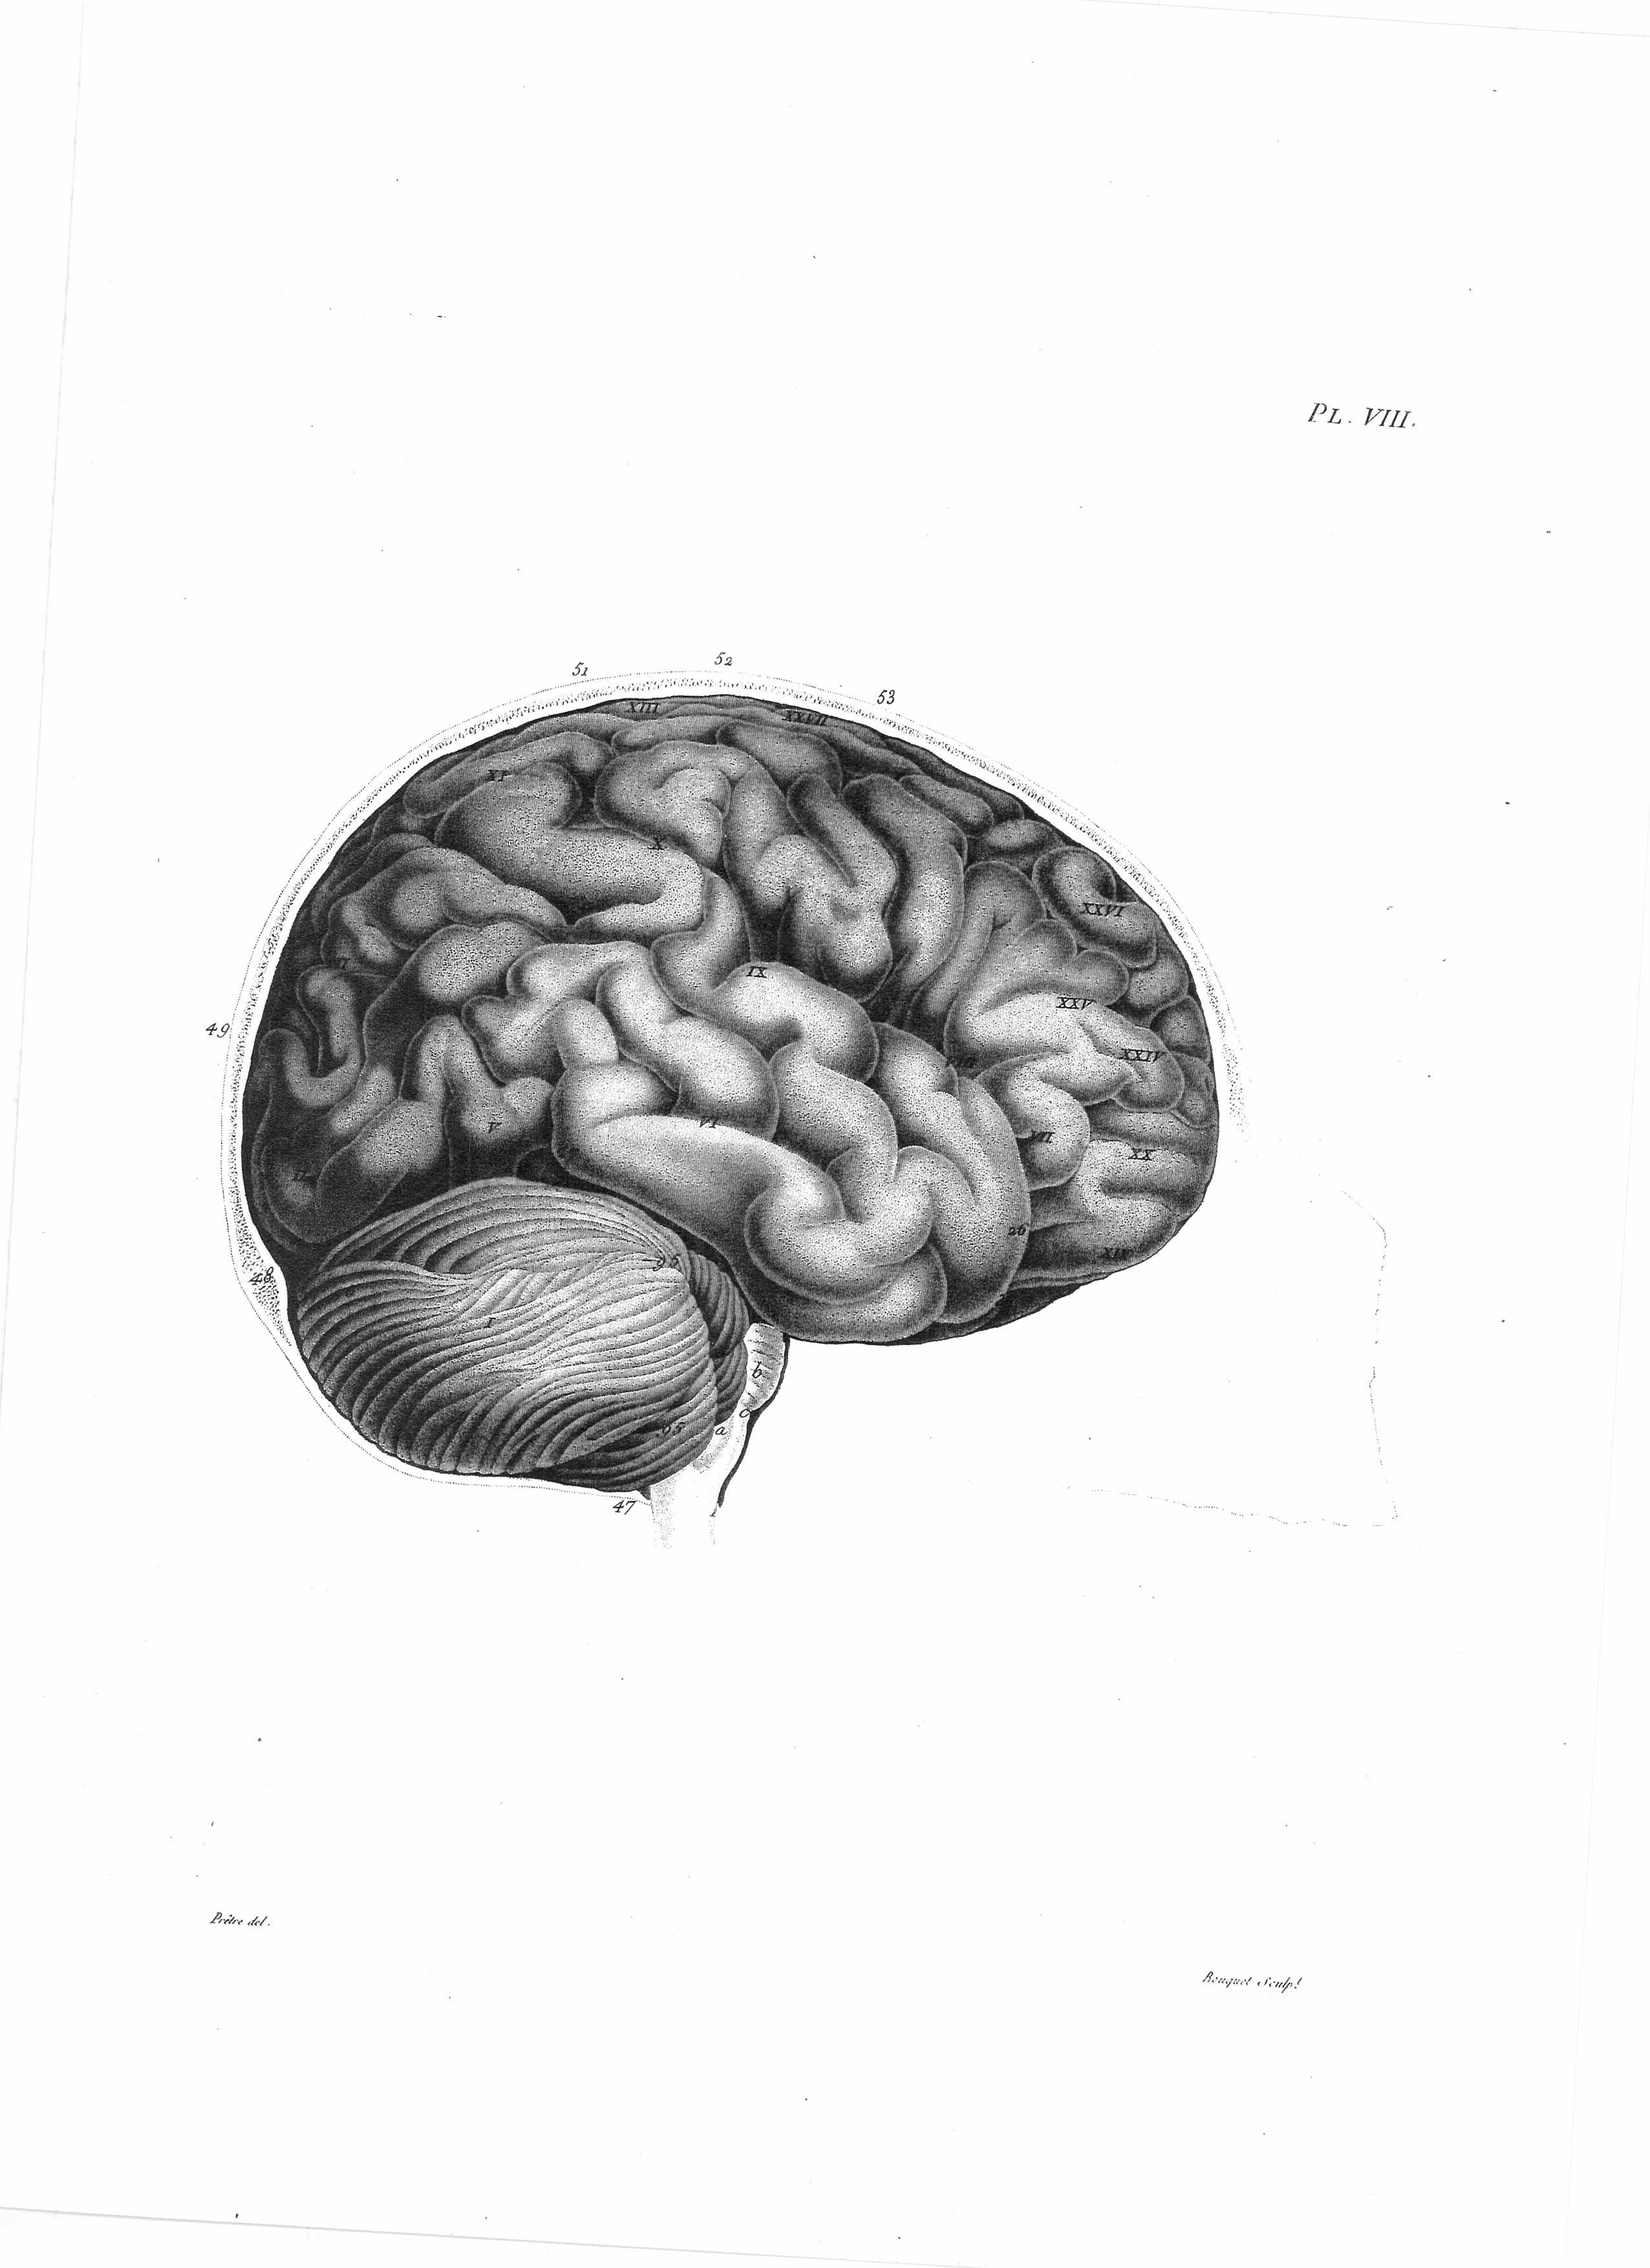

Gall: Plates

Gall, F. J. (1818). Anatomie et physiologie du système nerveux en général, et du cerveau en particulier, Avec des observations sur la possibilité de reconnoître plusieurs dispositions intellectuelles et morales de l´homme et des animaux, par la configuration de leurs têtes.

Librairie Grecque-Latine-Allemande, Vol. 3, I-XXXV u. 1-379 100 planches.